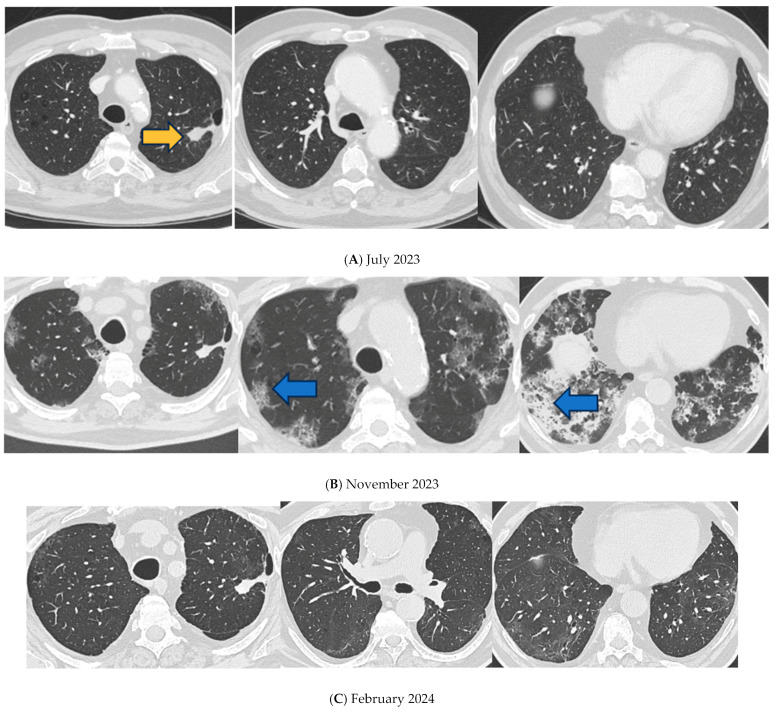

Pembrolizumab is used as a first-line treatment of non-small cell lung cancer. Pneumonitis and interstitial lung disease are among the most common immune-related adverse events. The impact of severe acute respiratory syndrome coronavirus 2 (SARS-CoV-2) infections on patients with cancer treated with chemotherapy or immune checkpoint inhibitors (ICIs) is not fully known. Blocking immune checkpoints may conversely augment dysfunctional T-cell responses in severe patients and, in turn, mediate immunopathology. Here, we present a case of SARS-CoV-2 infection complicated by acute respiratory distress syndrome (ARDS) and a fibrotic-like pattern in a patient treated with pembrolizumab for lung cancer. The patient showed a dramatic clinical and radiological response after steroid therapy. Further research is needed to better understand the long-term implications of pembrolizumab therapy in patients recovering from coronavirus disease 2019 (COVID-19) and to develop evidence-based guidelines for managing these complex cases. Patients undergoing oncologic immunotherapy might benefit from early high-dose steroid treatment in cases of viral infections, such as SARS-CoV-2.